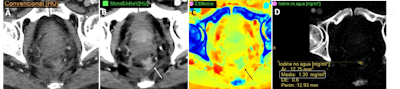

A 43-year-old man with right renal colic. (A) Conventional image shows a large stone in the right renal pelvis of indeterminate composition. (B, C) Spectral images confirm the presence of a uric acid stone. This is clinically relevant as uric acid calculi can be treated medically (urinary alkalinization), whereas other calculi (calcium, etc.) may require interventional procedures (stone removal or external shock wave lithotripsy). All figures courtesy of Dr. Ana Villanueva Campos et al and presented at RSNA 2023.